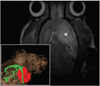

Methods: Transient cerebral ischemia was induced in adult Wistar rats (n=25) followed by IA or intravenous (IV) injection of mesenchymal stem cells (MSCs) labeled with superparamagnetic iron oxide. Cell infusion was monitored in real time with transcranial laser Doppler flowmetry while cellular delivery was assessed with MRI in vivo (4.7 T) and ex vivo (9.4 T).

Results: Successful delivery of magnetically labeled MSCs could be readily visualized with MRI after IA but not IV injection. IA stem cell injection during acute stroke resulted in a high variability of cerebral engraftment. The amount of LDF reduction during cell infusion (up to 80%) was found to correlate well with the degree of intracerebral engraftment, with low LDF values being associated with significant morbidity.

Conclusions: High cerebral engraftment rates are associated with impeded cerebral blood flow. Noninvasive dual-modality imaging enables monitoring of targeted cell delivery, and through interactive adjustment may improve the safety and efficacy of stem cell therapy.